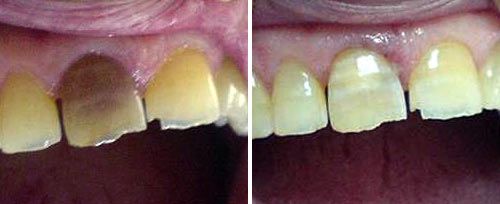

Tooth Whitening

Courtesy of: Carlo Fornaini, MD, DDS, M.Sc.

Laser source: Nd:YAG (1064 nm)

Courtesy of: Evgeniy Mironov, DDS

Laser source: Er:YAG (2940 nm)